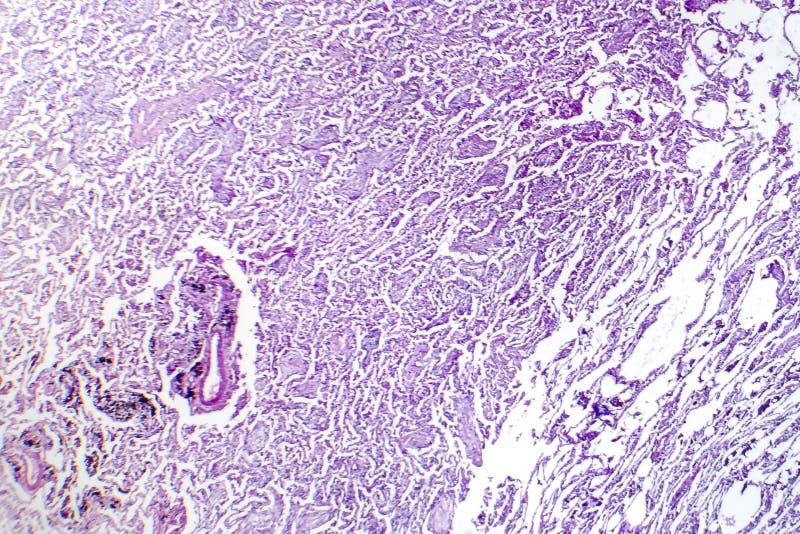

The ICD code J181 is used to code Lobar pneumonia

Lobar pneumonia is a form of pneumonia that affects a large and continuous area of the lobe of a lung.

Lobar pneumonia, also known as non-segmental pneumonia or focal non-segmental pneumonia 7, is a radiological pattern associated with homogeneous and fibrinosuppurative consolidation of one or more lobes of a lung in response to bacterial pneumonia.May 23, 2020